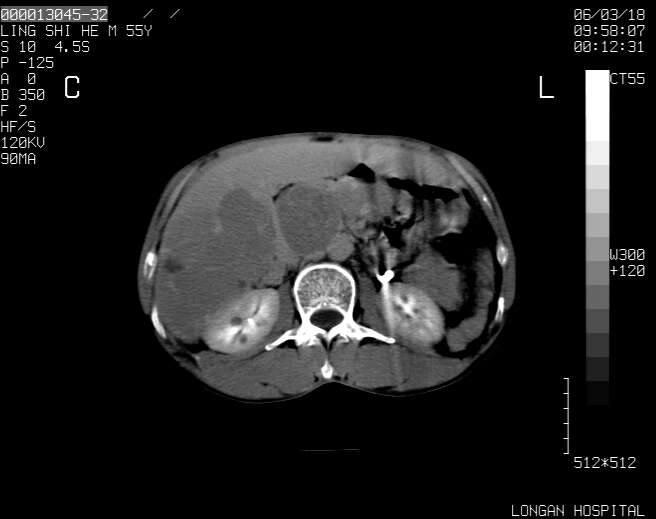

以下是引用guzhongliangddd在2006-3-21 22:13:00的发言:[br]病灶主要位于肝右叶的后份,内见异常血管,门脉主干及右支受侵{提示有癌栓形成},门腔间隙内见增大淋巴结。肝左叶内未见异常。

以下是引用zhuxinli在2006-3-22 1:23:00的发言:[br][br] 病灶主要位于肝右叶的后份,内见异常血管 .门脉右支截断,右叶前段早期强化(考虑动静脉漏),腹膜后肿大淋巴结,病灶逐渐强化,考虑为胆管细胞癌[br]